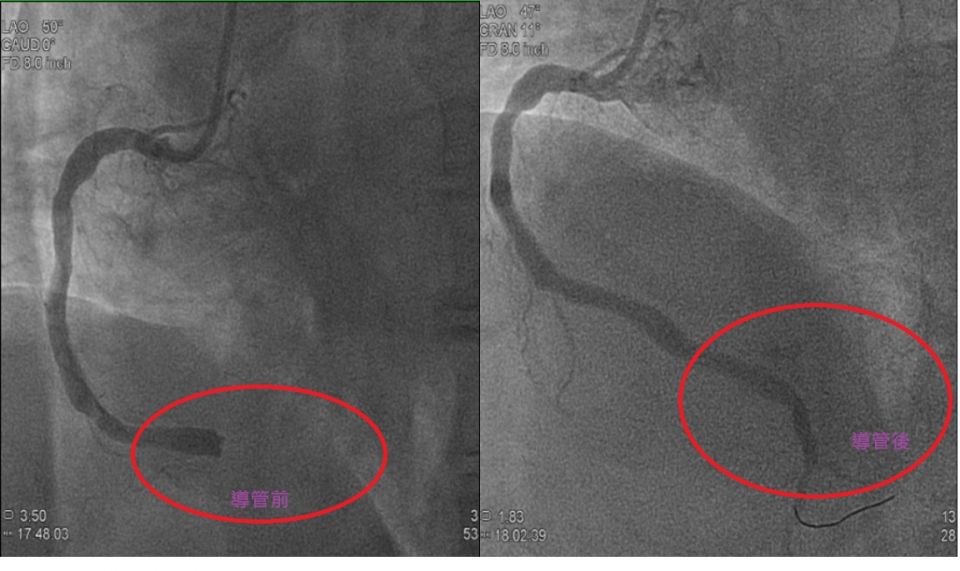

(記者鍾盛增/苗栗報導)42歲的陳姓男子日前上午因持續幾分鐘嚴重胸悶呼吸急促身體不適,旁人發現幫忙撥打119求救,救護人員在救護車上做心電圖,並上傳至「苗栗冠心症到院前救護團隊」線上群組,為恭紀念醫院心臟科團隊的線上醫師,立刻協助判讀為「心室纖維顫動(VF)」,並指導救護人員使用 AED去顫,但病患仍出現昏厥失去意識狀態,且無呼吸心跳,再緊急使用心肺復甦術急救。送達為恭醫院急診室後,立即啟動相關醫療程序從檢查到評估到治療一條龍串接,迅速送到心導管室由心臟內科褚佩寰副院長緊急心導管手術處置,經過氣球擴張術和支架置放術後順利打通血管,術後進加護病房觀察。

褚佩寰副院長表示,所謂的「心室纖維性顫動(Ventricular Fibrillation,VF)」是指心跳變得異常、心室顫動、不能輸出血液,人體因此很快會出現缺氧,病人幾秒鐘之內會失去知覺,當心臟的電訊號異常時,心臟無法輸出血液,心跳會停止!需要馬上啟動緊急心導管手術放置支架後打通阻塞的血管,也需要趕在腦部與其他器官因缺血、缺氧而壞死之前,恢復正常的血液循環,因此當發生心室纖維性顫動時,搶救的時間就是挽救的關鍵。